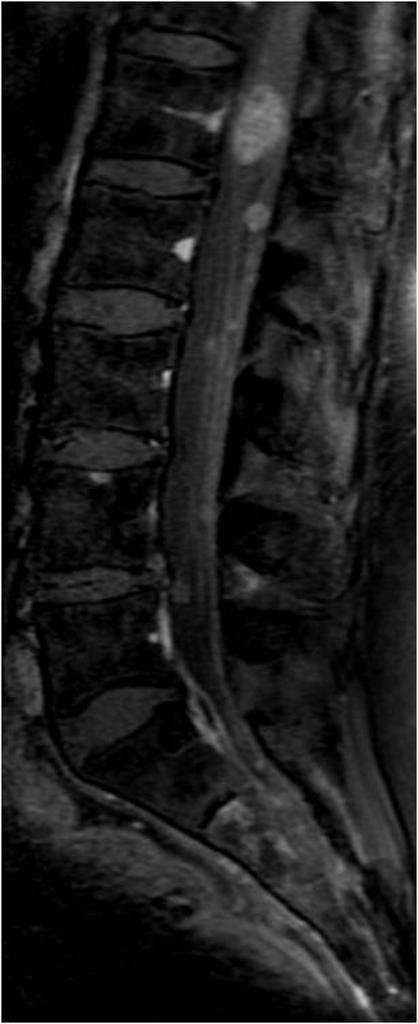

Lumbosacraal radiculair syndroom =

"Uitstralende pijn in één bil of been, al dan niet met andere prikkelingsverschijnselen en neurologische uitvalsverschijnselen, die suggestief is voor een prikkeling van één (of twee) specifieke lumbosacrale zenuwwortel(s)"2

Beeldvorming

• NHG (2015) NA 6 weken in samenspraak met patiënt2